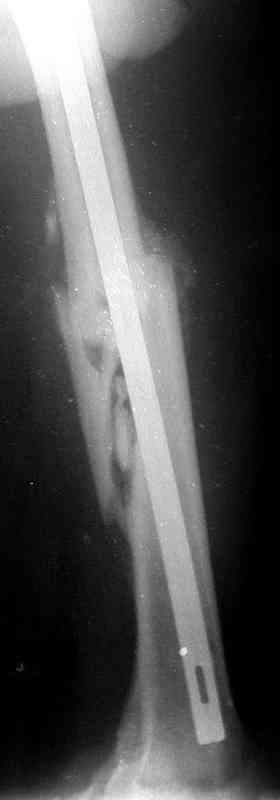

Больной А., 28 лет, поступил в НИИ им. Н.В. Склифосовского 22.12.99 после падения на улице. Жалобы на боли в области левого тазобедренного сустава и левом бедре. Из анамнеза следовало, что 20.06 во время прыжка с парашютом у него возник закрытый оскольчатый перелом средней трети левой бедренной кости со смещением отломков, по поводу чего в одной из ЦРБ Московской области через 3 дня после травмы был произведен открытый интрамедуллярный остеосинтез штифтом типа Кюнчера.

по его наружной поверхности послеоперационный рубец - рана зажила первичным натяжением. При измерении длины бедер обнаружено укорочение левого бедра на 4,5 см. На рентгенограммах этого бедра: ось конечности правильная, отмечается захождение основных костных фрагментов по длине, проксимальный конец штифта выступает слишком медиально и высоко относительно большого вертела, периостальная мозоль незначительна.22.12 - через 6 месяцев после операции, произведенной в ЦРБ, нами по поводу замедленно консолидирующего перелома левой бедренной кости с ее абсолютным укорочением под наркозом произведена операция: удаление штифта, закрытый блокирующий интрамедуллярный остеосинтез перелома левого бедра штифтом без рассверливания (UFN) длиной 40 см, диаметром 10 мм с блокированием только проксимальных отверстий (динамический остеосинтез). Наложен аппарат Илизарова на 4 полукольцах с целью удлинения укороченного бедра. Послеоперационное течение без особенностей. Ежедневно осуществляли дистракцию отломков на 1 мм. Через 3 недели после операции больной выпи-сан на амбулаторное лечение с продолжением дистракции отломков. В течение 1,5

месяцев дистракции укорочение левого бедра удалось полностью устранить. 22.02.00, т.е. через 2 месяца после повторного остеосинтеза, больному произведено дистальное блокирование штифта двумя винтами и демонтирован аппарат Илизарова. В течение 2 недель после операции больной ходил с помощью костылей, потом 2 недели с тростью. Опороспособность и функция оперированной конечности полностью восстановились через 4 недели после операции.